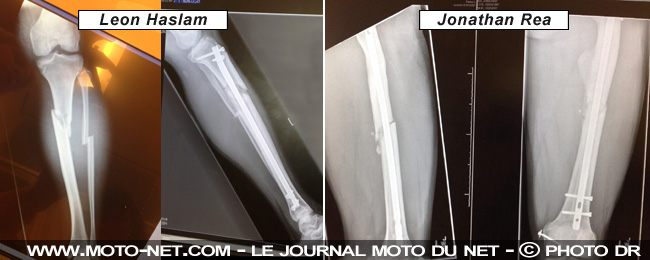

Confirmés avant même la fin de la saison 2013, Jonathan Rea et Leon Haslam se rendront en Espagne avec leur équipe Honda Pata. Tous deux blessés aux jambes la saison dernière, "JR" et la "Pocket Rocket" espèrent que la malchance ne les poursuivra pas en 2014.

Blessé plus tôt dans la saison (dès la troisième épreuve Assen, Leon Haslam a été contraint de mener de front courses et récupération... "Honnêtement, cette blessure était de loin la pire que je n'ai jamais eue", assure le second pilote Honda Pata, tout juste trentenaire.

"Pas tant au niveau des fractures (tibia et fibule, juste sous le genou gauche, NDLR) qu'à celui des dommages causés au tissu et au manque de puissance de ma jambe ensuite", précise le n°91 qui espère être totalement remis avant l'ouverture de la saison 2014 à Phillip Island et continuera d'ici là à travailler d'arrache-jambe-pied sur la CBR1000RR...